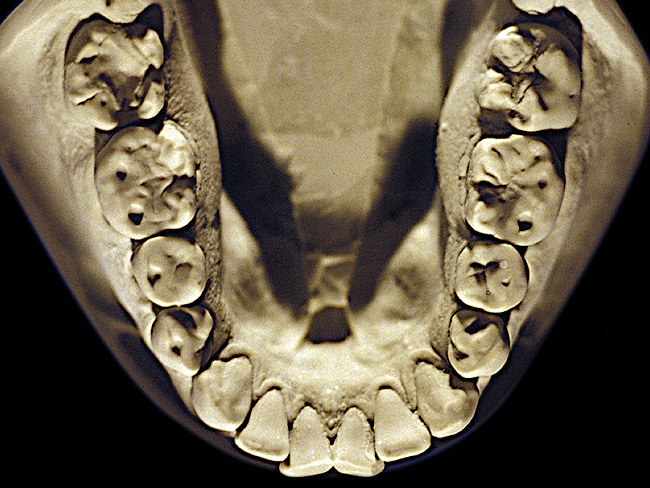

Figure 12  Advanced NCLTS from toothpaste, mandibular arch.

Figure 12

So that the previous example is not misleading, the behavioral profile of the toothpaste abuser is not necessarily the "caries-free immaculate oral hygiene patient," but can be virtually anyone who brushes their teeth with toothpaste. Figure 11 and Figure 12 illustrate a more advanced example of toothpaste abuse showing a patient with multiple restorations and some unkempt teeth. The anatomical details were faded with a sandblasted appearance and the silver alloy restorations were highly polished. The facial surfaces of the mandibular canines and premolars were affected the most, creating the pathognomonic pattern. Figure 13 and Figure 14 are a close-up view of this area, illustrating a cupping or cratering effect, but of the asymmetrical variety. This patient did not like the color of his teeth and spent an inordinate amount of time brushing his teeth. Again, likewise due to the exclusive use of a round-ended, soft-bristle toothbrush, note there was no cervical gingival recession in this case either. When the featured casts illustrating toothpaste abuse (Figure 7, Figure 8, Figure 9, Figure 10, Figure 11, Figure 12, Figure 13 and Figure 14) were hand-articulated, the worn surfaces did not match up and the diagnosis of toothpaste abuse was confirmed.